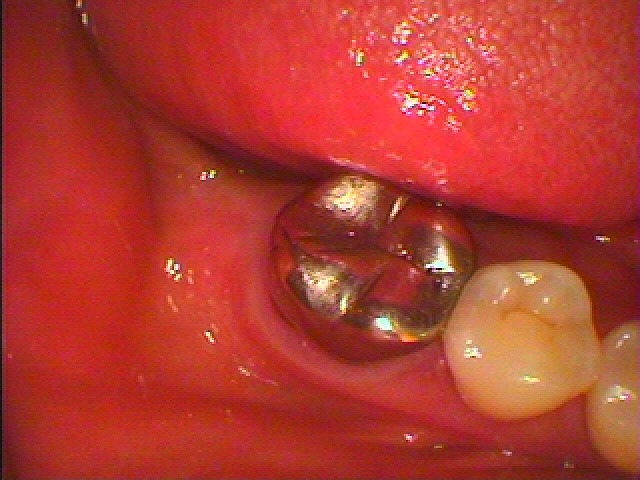

ブログ一覧|広島市安佐南区の歯科医院 ブログ一覧 トップ ブログ一覧 お知らせ スタッフブログ ブログ一覧 お知らせ 2024/05/01 60代女性 昔から少しずつ前歯が隙間が空いてきた 葉はあまり削りたくないけど何とかならないかが相談 佐伯区と安佐南区の境にあるこころ団地内のこころ歯科クリニックの臨床現場 お知らせ 2024/04/30 左下の奥のブリッジが取れた 食事ができない 診てほしい ブリッジがダメになった時のインプラント治療 60代女性 佐伯区と安佐南区の境にあるこころ団地内のこころ歯科クリニックの臨床現場 お知らせ 2024/04/30 右上の4番部が歯茎が腫れたり、噛むと痛む 歯の同様が主訴になります 佐伯区と安佐南区の境にあるこころ団地内のこころ歯科クリニックの臨床現場 お知らせ 2024/04/27 インプラントは術前のCT精査にてほぼ予後が悪いかが判断できます それをもとにインプラント可能かどうか、いろいろと精査していきます 安佐南区と佐伯区の境にあるこころ団地内のこころ歯科クリニックの臨床現場 お知らせ 2024/04/27 左上の4番部が噛むと痛むし、歯茎が腫れるようになってきたとのこと 診てほしい ブリッジかインプラントかで今回は歯がまた割れると嫌なのでインプラントを選択 佐伯区と安佐南区の境にあるこころ団地内のこころ歯科クリニックの臨床現場 お知らせ 2024/04/26 前歯部のブリッジが動く 診てほしい それと歯が長いのがもう少しどうにかならないか? 佐伯区と安佐南区の境にあるこころ団地内のこころ歯科クリニックの臨床現場 お知らせ 2024/04/26 右下の7番部のインプラント埋入 骨の高さもとりにくくインプラント最難関部位といつも思っています 佐伯区と安佐南区の境のこころ団地にあるこころ歯科クリニックの臨床現場 お知らせ 2024/04/25 右下奥の最難関インプラント埋入 歯は咬合圧の高さもあって、破折したり歯周病で失われる傾向が格段に高いです << 1 2 3 4 5 … 58 59 60 61 62 … 870 871 872 873 874 >> Web診療予約 初めての方へ 選ばれ続ける理由 院内設備について 歯が痛いしみる一般歯科 歯がぐらぐらする歯周病 健康な歯を保ちたい予防歯科 子供の虫歯予防をしたい小児歯科 銀歯をセラミックに審美歯科 白い歯を目指しませんか?ホワイトニング 矯正専門医がいるので安心矯正歯科 抜けた歯を補いたいインプラント・入れ歯 医院案内 スタッフ紹介 メリィハウス歯科クリニックオフィシャルホームページ ラベンダー歯科クリニックオフィシャルホームページ お知らせ・ブログ ホーム 診療科目 一般歯科 歯周病治療 予防治療 小児歯科 審美治療 ホワイトニング 矯正歯科 入れ歯・インプラント マウスピース矯正 初めての方へ 院長・スタッフ 設備紹介 医院案内・アクセス メニューを閉じる